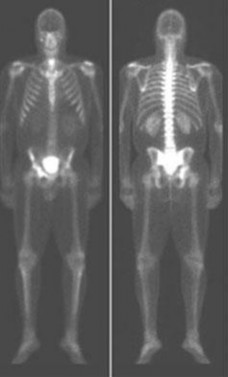

A 65-year-old male who underwent a cementless total hip arthroplasty (THA) 15 years ago presents with new-onset thigh pain. Radiographs reveal eccentric positioning of the femoral head within the acetabular shell and large retroacetabular and proximal femoral radiolucencies.

What is the primary biological mediator released by macrophages that directly stimulates osteoclastogenesis and is responsible for the observed bone loss?

Explanation

The radiograph demonstrates particle-induced osteolysis, secondary to polyethylene wear debris. When macrophages phagocytose these particles, they release pro-inflammatory cytokines, most notably TNF-a, IL-1, and IL-6. These cytokines stimulate the RANK/RANKL pathway, activating osteoclasts and leading to significant periprosthetic bone loss. IL-10 and IL-4 are anti-inflammatory cytokines, while IFN-y actually inhibits osteoclastogenesis.